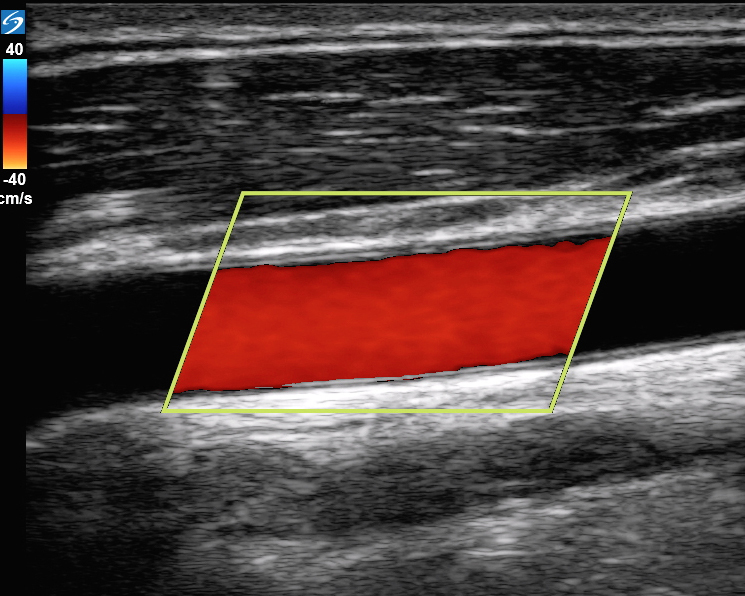

彩色血流图像中的颈动脉